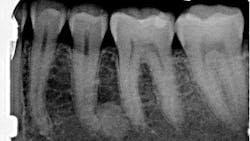

A healthy 41-year-old female presented to the office for a routine exam and checkup. Her health history was normal, and she reported no major concerns or issues.

Radiographic examination revealed a large, radiopaque mass just distal to the apical third of tooth no. 20. The area was not tender to palpation, and the tooth tested vital and WNL.

Periapical idiopathic osteosclerosis

The lack of radiolucent border and the unknown etiology of the lesion strongly indicate that this lesion is periapical idiopathic osteosclerosis. Since there are no previous radiographs to reference, this diagnosis is not concrete. This diagnosis presents no clinical significance; hence, the patient will be reexamined periodically. Any changes and subsequent treatment will be rendered.